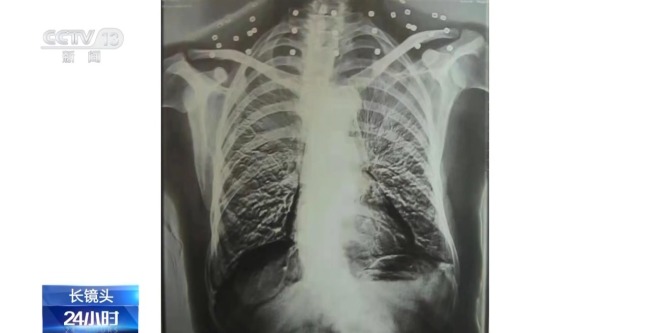

这张CT照片是82岁吴以先老人的CT照,当初拍片时,医生说,“老先生,您要把项链取下来再做CT。”吴以先老人跟医生说,“可我从来没戴过项链,怎么会有项链呢?你看会不会是弹片?”自此,引出了一段老人不平凡的往事。

吴以先:21、22、23、24、25、26、27、28、29、30、33个,还有其他地方有,这里还有一个弹片。

记者:腹部还有弹片。

吴以先:腹部有弹片,加起来是33个。

二十年前,吴以先老人做CT检查时发现,他的颈部有许多弹片,医生当时把弹片误认为是老人戴的项链,于是提醒他要把项链取下来再做检查。

吴以先:体检医生发现的,他一看,他说像一串项链一样的,他说你看这个病人脖子上的项链都没有取下来,好大一串项链。我说我从来没有戴过项链,这不是项链吧,我说是不是弹片,你们看看。

这是吴以先老人体内的33颗弹片,也是老人摘不下来的“项链”。